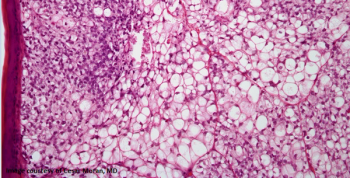

A 54-year-old woman is found to have a skin lesion in the right arm. What is your diagnosis?